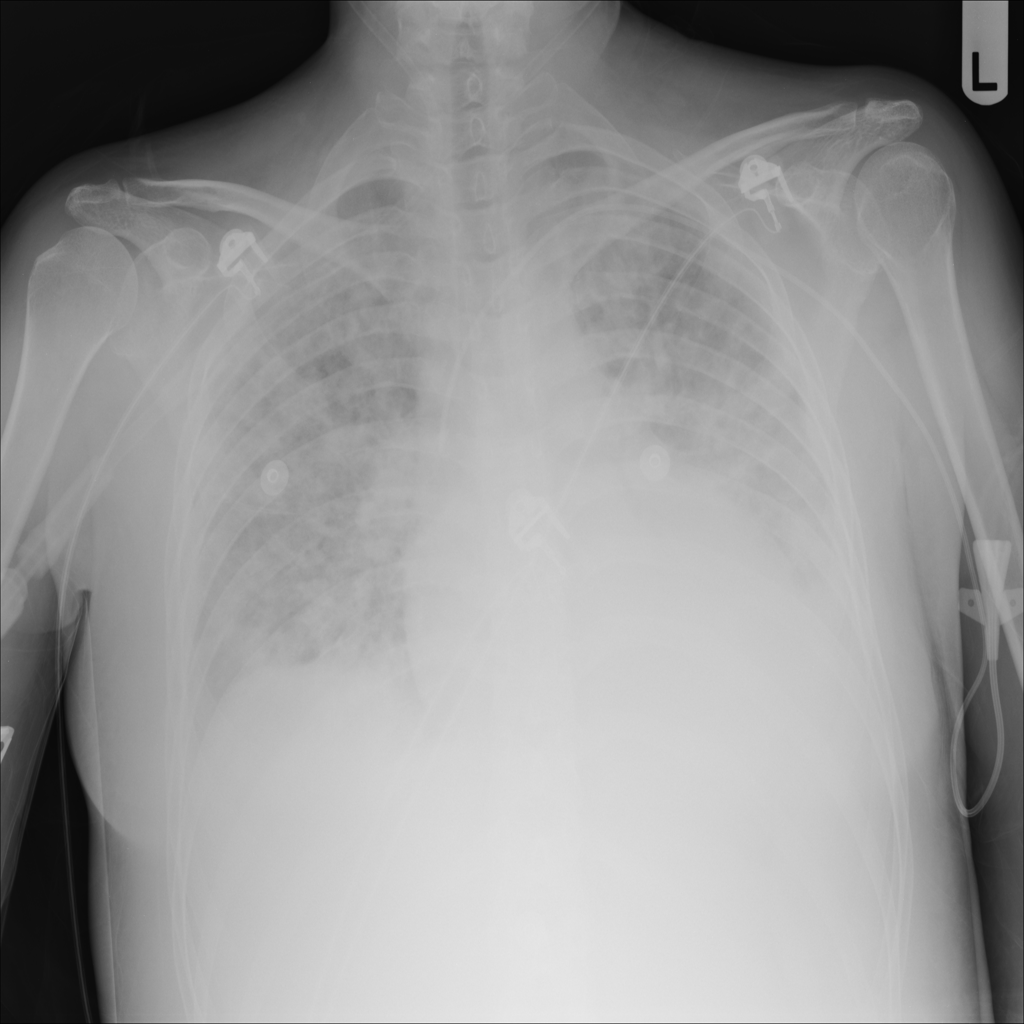

PAT-B3C3 · IMG-001Pneumonia

PAT-B3C3 · IMG-001

PA